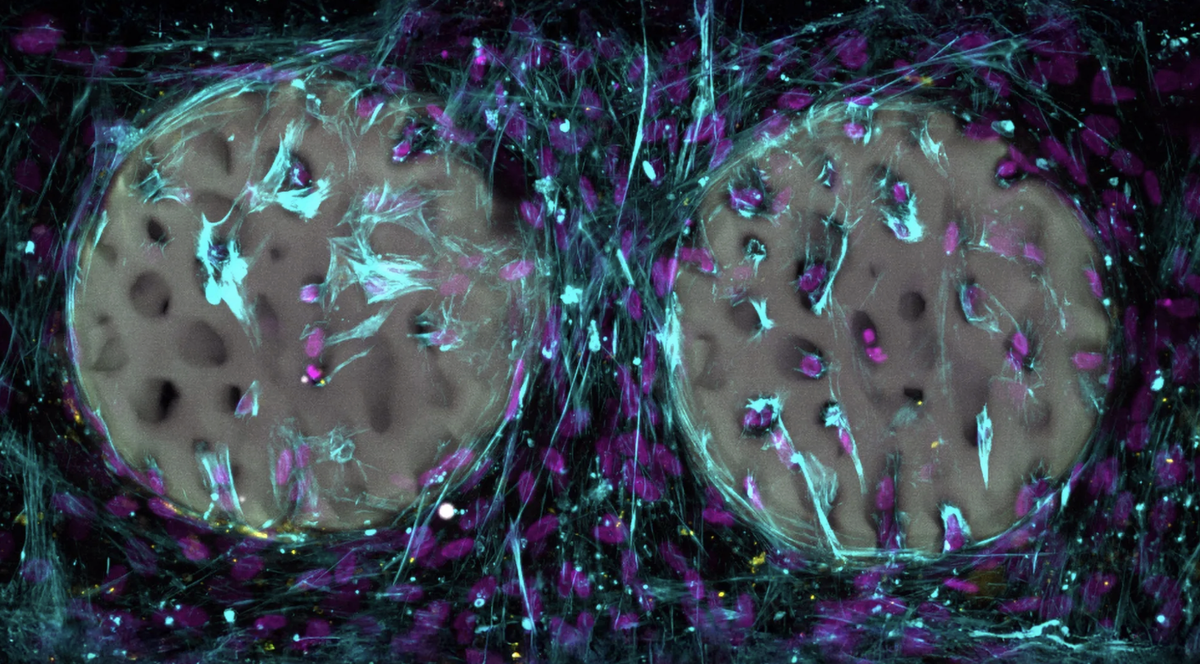

Гидрогель имитирует раннюю стадию естественного заживления. Когда кость ломается, сначала образуется мягкий каркас — гематома с сетью фибрина, куда мигрируют клетки восстановления. Только позже эта структура превращается в твёрдую ткань. Швейцарские исследователи добавили в гель специальные молекулы: одна связывает полимерные цепи, другая активируется светом. Под действием лазера материал мгновенно твердеет в нужных точках, а неосвещённые участки остаются мягкими и удаляются.

В лабораторных тестах костные клетки активно заселяли напечатанную структуру и начинали вырабатывать коллаген — ключевой компонент костной ткани. Материал уже запатентован, а следующим шагом станут испытания на животных совместно с AO Research Institute Davos.